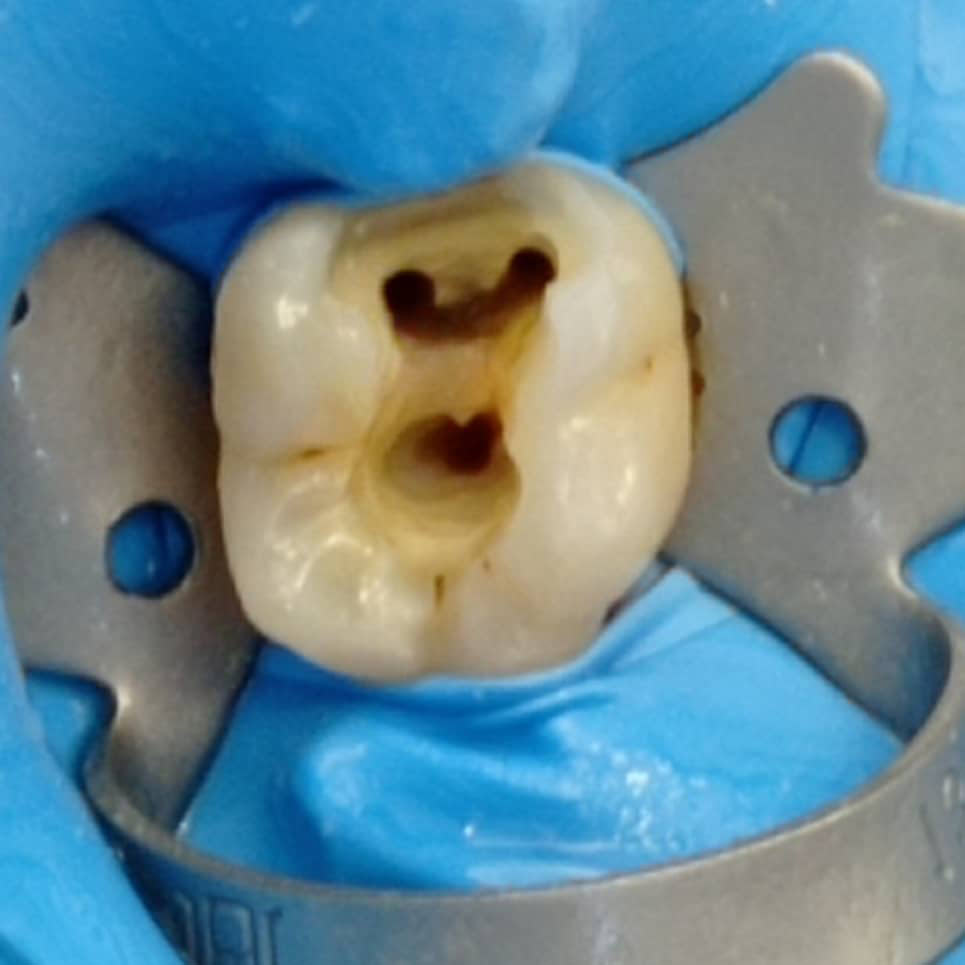

Η απονεύρωση, γίνεται όταν πλέον το δόντι έχει νεκρωθεί για κάποιο λόγο, βλέπε φλεγμονή, κάταγμα, εκτεταμένη τερηδόνα, είτε γιατί έχει σπάσει αρκετά και πρέπει στα πλαίσια της αναπλήρωσης του και αποκατάστασης να απονευρωθεί για να διατηρηθεί σωστά στο στόμα μας, είτε γιατί έχει κάποια κύστη.

Είμαστε εξειδικευμένοι ~ με ετήσια μετεκπαίδευση στον τομέα των απονευρώσεων ~ και πραγματοποιούμε τις θεραπείες μας, με όλα τα τελευταία μέσα και τεχνολογία, πλήρως εναρμονισμένοι, ενημερωμένοι, για το μέγιστο άρτιο αποτέλεσμα.

Απονεύρωση, χωρίς να σπάσουν τα νεύρα σας! ~ Άμεσα, ακίνδυνα, αποτελεσματικά.